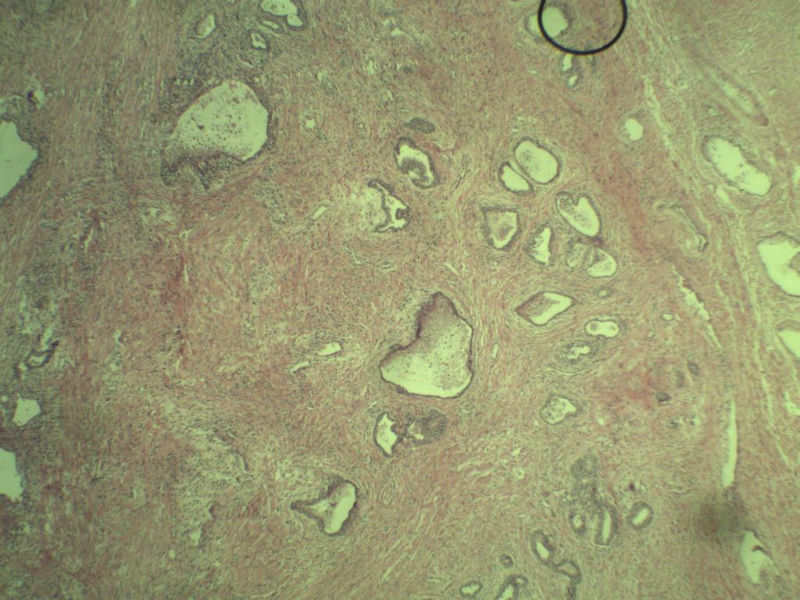

男 75岁 因排尿困难半年行前列腺切除术,体积 4 × 3 × 2.5 cm3,切面灰白,实性,质韧。请各位老师看看 有问题没? 谢谢了!

高级别上皮内瘤变,建议免疫组化:P63、34BE12、P504S

前列腺增生症伴鳞化

良性前列腺增生

良性前列腺增生伴尿路上皮化生

前列腺增生伴尿路上皮鳞化及Brown巢形成,未见恶性。